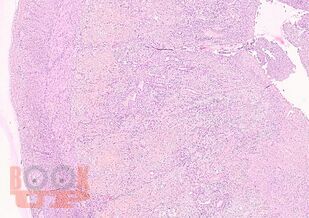

В учебном пособии представлен теоретический материал, перечень макропрепаратов и микропрепаратов, демонстрирующих типовые проявления патологических процессов. В цветных иллюстрациях и в описании микропрепаратов сделан акцент на наиболее важных гистологических изменениях, позволяющих на светооптическом уровне диагностировать и дифференцировать состояния, отклоняющиеся от нормы, в том числе с использованием различных гистологических окрасок. Пособие помогает выделить главные аспекты изучаемых патологических процессов, организовать и конкретизировать учебный процесс.